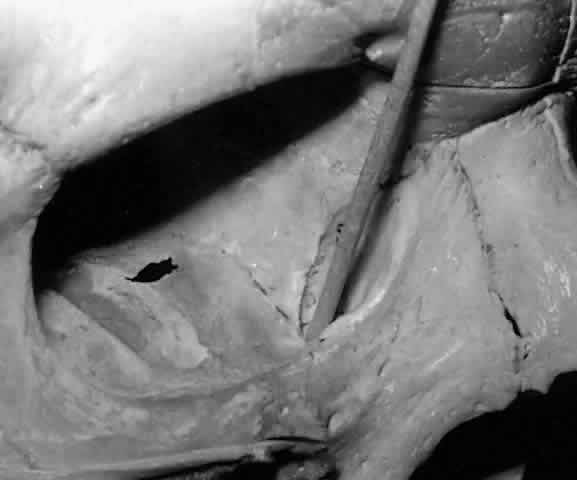

The parenchyma of the gland is made up of small lobules separated by a fine connective tissue network. The lacrimal gland has approximately 12 secretory ducts (Fig. 7), which average 0.66 mm in diameter and 2.31 mm in length.4 Two to five of them originate from the orbital lobe and six to eight from the palpebral lobe. The ductules from the orbital portion of the lacrimal gland pass through the parenchyma of the palpebral lobe before exiting into the superotemporal portion of the conjunctival fornix 4 or 5 mm above the upper border of the tarsus. One or two may open near the lateral canthus.5 Excision of the palpebral lobe may therefore interrupt drainage from the orbital lobe as well.

Fig. 7. Secretory ducts (arrow 1) of the right lacrimal gland (arrow 2) are seen passing to the palpebral conjunctiva (arrow 3). (Courtesy of James Sanderson, MD, Orkan Stasior, MD, and George Stasior, MD)